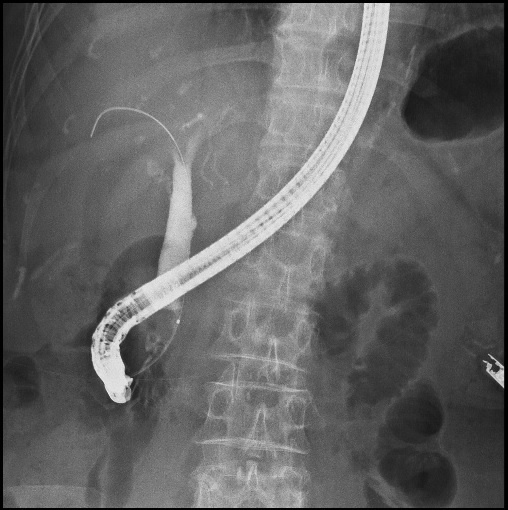

ERCP画像

血管造影検査

血管内にカテーテルを挿入し造影剤を入れて血管を撮影します。血管内治療も行っています。